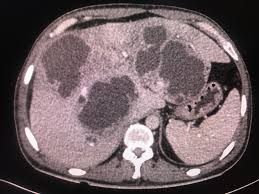

Triangular echogenic area in the anterior aspect of the kidney. Carter ar horgan jg jennings ta rosenfield at. Junctional parenchymal defect jpd is a triangular or linear hyperechoic structure in the anterosuperior or posteroinferior surface of the kidney. A triangular echogenic area in the upper pole renal parenchyma can be identified at times during routine sonography of the right kidney.